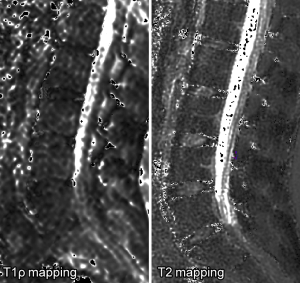

Spinal magnetic resonance imaging (MRI) was performed on all volunteers using a 1.5 T scanner (Achieva, Philips Healthcare, Best, Netherlands) with a 16-channel spine coil (SENSE-SPINE; Philips). The volunteers remained in the supine position with their legs extended and relaxed. Spin-echo sequences were acquired in the sagittal plane to generate quantitative T2 and T1ρ relaxometry maps using identical geometric parameters: FOV =22 cm × 22 cm, thickness =4 mm, slices =16, matrix =256×256 and no gap between slices. The following contrast parameters were used: T2 multiecho sequence, TE =20/40/60/80/100/120/140/160 millisecond (ms) and TR =3,000 ms; T1ρ-prepared MS turbo spin echo sequence, TE =20 ms, TR =2,000 ms, Single phase spin lock (SL) pulse, SL frequency =250 Hz, TSL =2/10/20/40/60 ms. The total image acquisition time was 13 minutes and all exams were acquired on afternoon period.

We used MINC tools and Display software (McConell Brain Imaging Center, Montreal, Quebec, Canada) to analyze the images. The relaxometry maps were generated using homemade scripts based on MINC tools from the corresponding data. T1ρ and T2 maps were computed on a pixel-by-pixel basis using an exponential decay model (Figure 1). S0 and S(TSL) are the equilibrium magnetisation signal and T1rho-prepared magnetisation signal with the spin-lock time of TSL. S(TE) is the signal acquired with the echo time (TE):